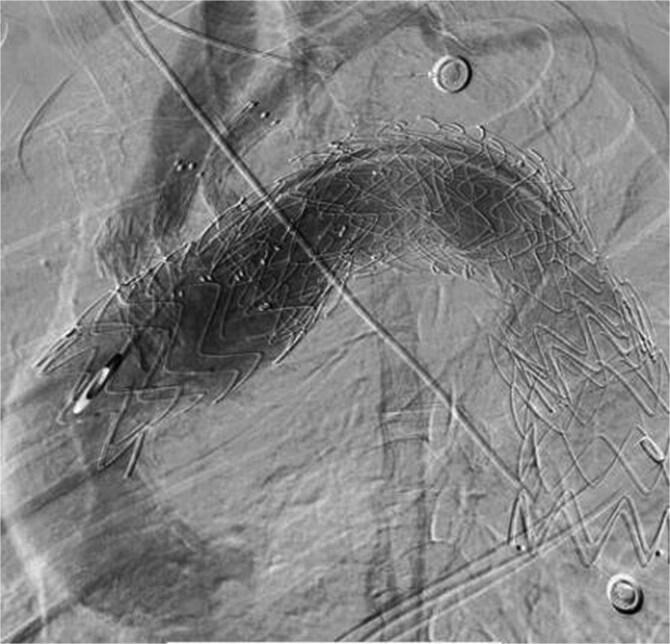

A 68-year-old male patient was hospitalized with a giant arch aneurysm. Using 3D printing guidance, the aneurysm was successfully sealed, but post-surgery, he developed severe complications. He remained in the intensive care unit for 52 days for observation and was discharged for rehabilitation. During follow-up, recurrent blood in sputum prompted a computed tomography scan revealing intracavitary leakage. After multiple treatments and assessments, it was determined that type IV endoleak resulted from the proximal bare stent graft puncturing the membranous portion of the aortic stent. Subsequent stent graft procedures and precise embolization successfully closed the leakage, resolving the symptoms.